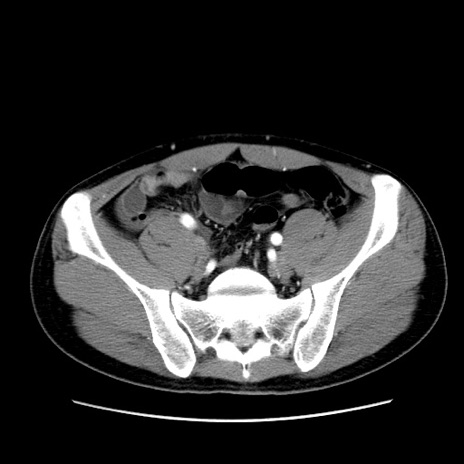

症例36(横断像)

【症例】20歳代 男性

【主訴】心窩部痛

【現病歴】今朝より上腹部痛あり。一旦軽快していたが再度出現したため救急要請。昨日夕に白身の魚を含む刺身を食べた。

【身体所見】BP 136/89mmHg、HR 74/min、BT 37.0℃、腹部:膨満、軟、心窩部に圧痛あり。反跳痛なし、筋性防御なし、腸雑音やや亢進あり。

【データ】WBC 17700、CRP 0.48